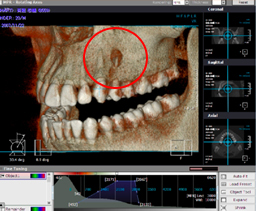

根尖病変(根の先の病気)

口腔内写真とデジタルXray写真(2次元)

CT 3D画像

3枚の写真赤丸部分が根尖病変(根の先の病気)です。

根の先に膿がたまっています。

デンタルXray写真(2次元画像)では理解しづらい根の先の骨吸収がCT画像(3次元画像)により明瞭に認められ確実な診査・診断が出来、患者さんの理解も容易になり1つの目標に向かって歯科医と患者が一体となりスムーズに治療を進めることが出来ます。